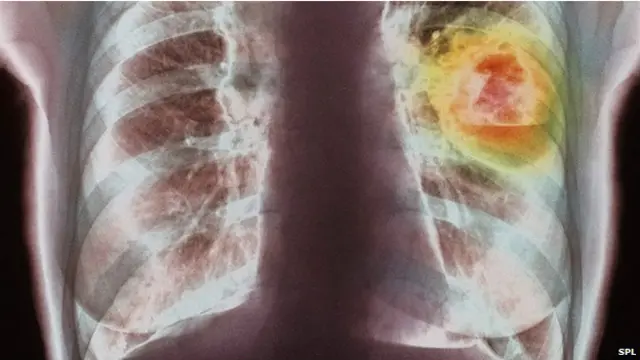

Рак легень, який виникає, головно, через куріння, є найпоширенішим у світі типом онкологічних хвороб. На нього хворіють 1,8 млн людей, або 13% від загальної кількості онкопацієнтів.